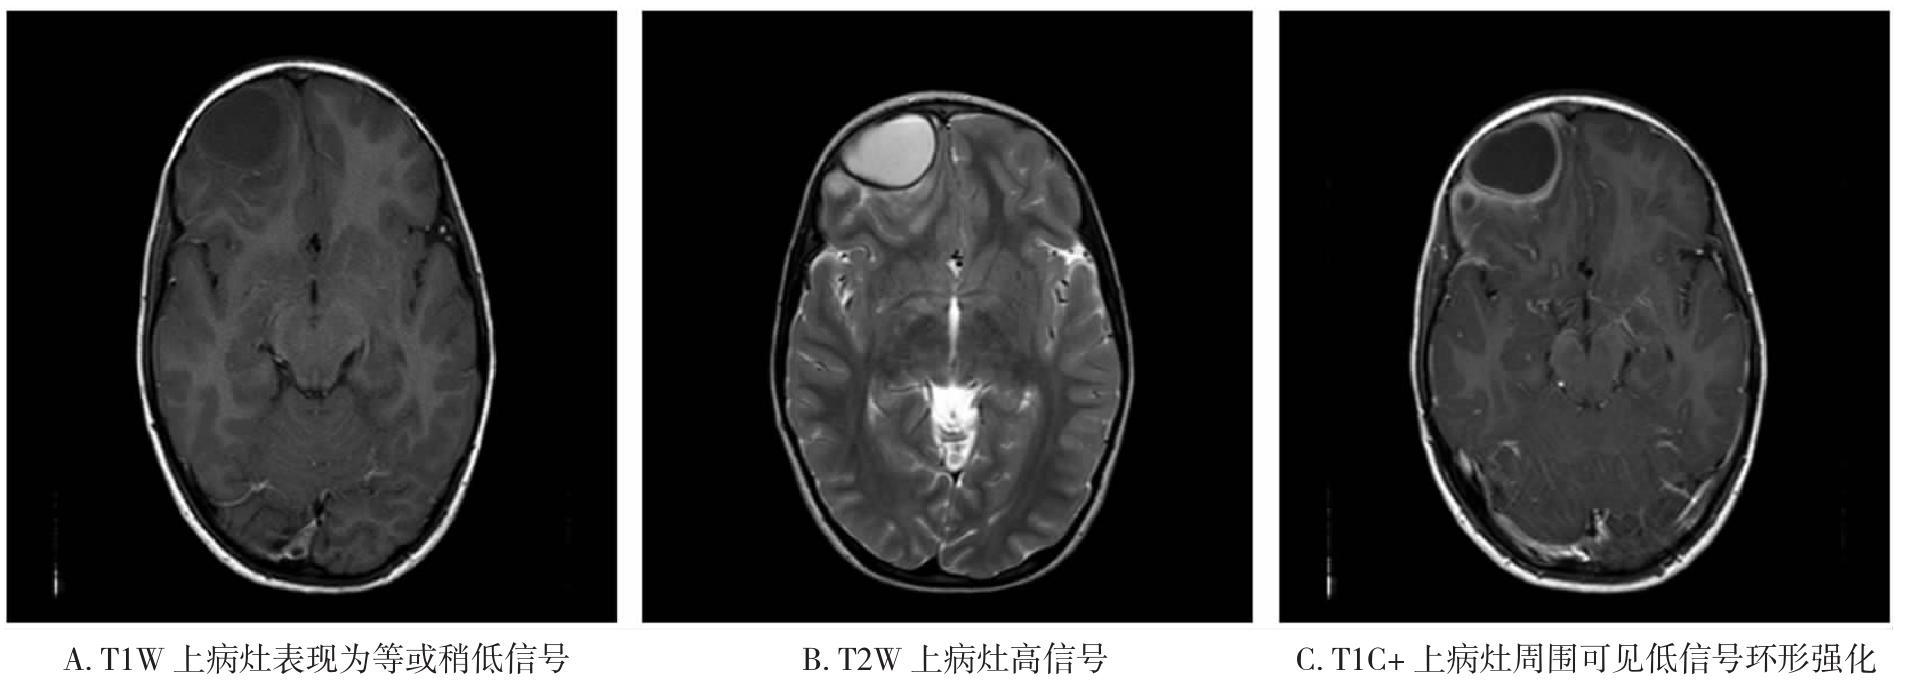

• 皮质基底节变性的影像诊断研究进展

2021, 46(7):818-822. DOI: 10.13406/j.cnki.cyxb.002866

摘要 (70) HTML (289) PDF 1.30 M (184) 评论 (0) 收藏

摘要:皮质基底节变性(corticobasal degeneration,CBD)是一种以不对称的运动症状和大脑皮质功能障碍为主要表现的神经退行性疾病。金标准为病理诊断,临床特征的异质性以及与其他神经退行性疾病在症状和病理方面的重叠性使得诊断难度大。现行诊断标准正确率较低,未将影像学纳入其中。本文主要综述近几十年CBD的影像学进展,包括计算机断层扫描(computed tomography,CT)、磁共振成像(magnetic resonance imaging,MRI)、放射性核素显像等,以及其在疾病鉴别方面的贡献。